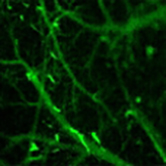

圖2:小鼠腦血管顯微成像

- 成像深度深:能夠輕松突破傳統(tǒng)成像的深度限制,深入生物組織內(nèi)部,為我們揭示那些隱藏在深處的秘密。在神經(jīng)科學研究中,它可以穿透顱骨,清晰地觀察大腦內(nèi)部的神經(jīng)結(jié)構(gòu)和活動。

- 生物醫(yī)學研究:在腫瘤檢測與治療研究中,它可以幫助我們實時監(jiān)測腫瘤的生長、轉(zhuǎn)移和對治療的響應,為個性化治療方案的制定提供依據(jù)。在神經(jīng)科學領(lǐng)域,能夠觀察神經(jīng)信號的傳遞和神經(jīng)網(wǎng)絡的活動,為神經(jīng)系統(tǒng)疾病的研究和治療開辟新的途徑。此外,在心血管疾病、免疫學等方面,也能發(fā)揮重要作用,助力科學家們攻克一個個醫(yī)學難題。